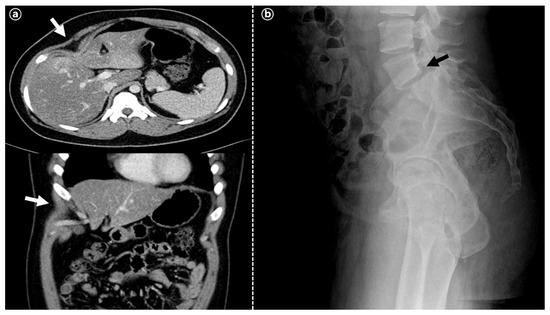

| Skeletal features | Short left 4th metacarpal bone | Mild kyphosis, pectus carinatum | (-) | NA | 8th rib cage deformity, spondylolisthesis of L5 on S1 |